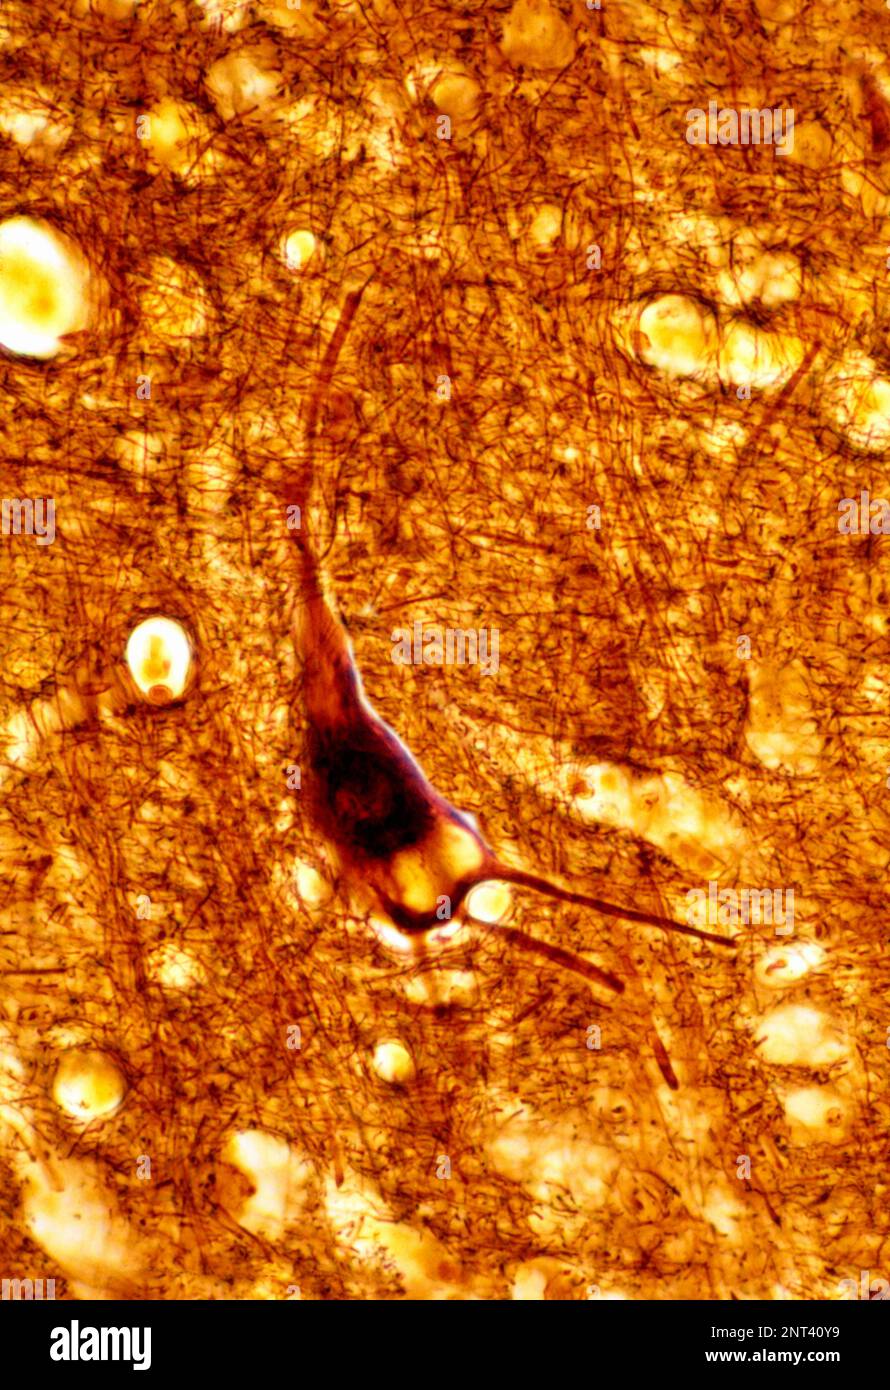

Die Hirnrinde ist jedoch nicht nur makroskopisch sichtbar, sondern vor allem auch ein mikroskopisch definierbarer Hirnabschnitt. Die Hirnrinde enthält vornehmlich „graue Nervenzellen“ (Substantia grisea) an der Oberfläche des Hirnorgans (die geschlängelten, dunkelgrau gezeichneten Randzonen in Abb. 2; vgl. auch Hirnrindenkarte). Die Dicke der grauen Substanz schwankt zwischen 1,5 und 4,5 mm. Im Gegensatz dazu enthalten die tieferen Hirnabschnitte den weißen Markmantel (Substantia alba). Dieser „weitere Mantel“ wird bisweilen auch Marklager genannt. Es besteht vorwiegend aus den langen Nervenzellfortsätzen, den Neuriten. Der graue und der weiße Mantel umhüllen gemeinsam die Stammganglien und die Ventrikel.